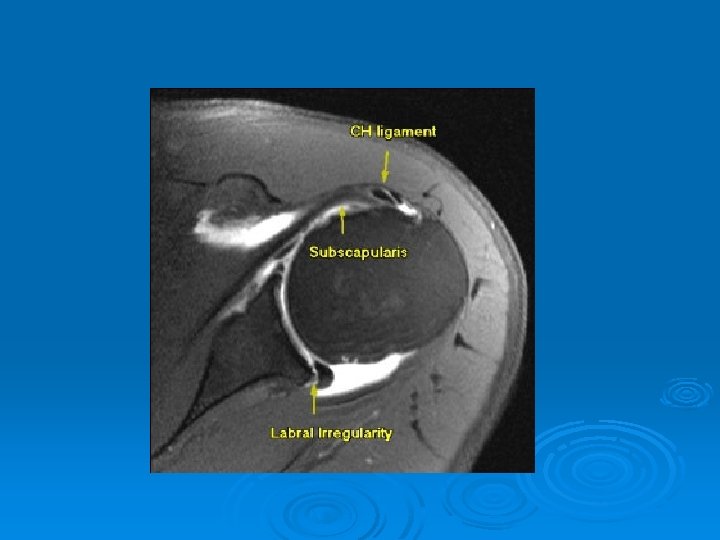

Dislocations Ø Most commonly traumatic and anterior Ø Postion of vulnerability (Abduction/ER) Ø 70% recurrence rate in patients under 22 Ø Independent of length of immobilization and physical therapy Ø Usually have a Bankart lesion (detached labrum) Ø Correlation between number of dislocations and soft tissue injury

Bony Bankart